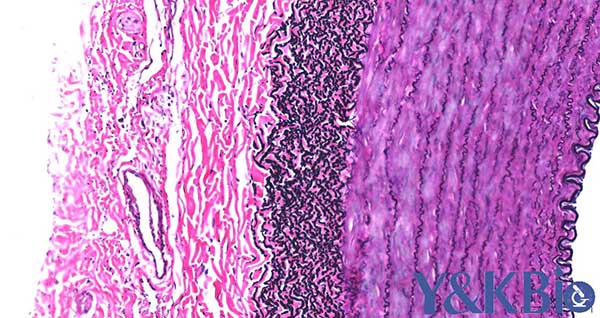

四、EVG染色

适用于血管、皮肤、肺 石蜡切片 ,观察弹力纤维、胶原纤维

染色结果: 弹力纤维呈紫黑色,胶原纤维呈红色,其它呈黄色